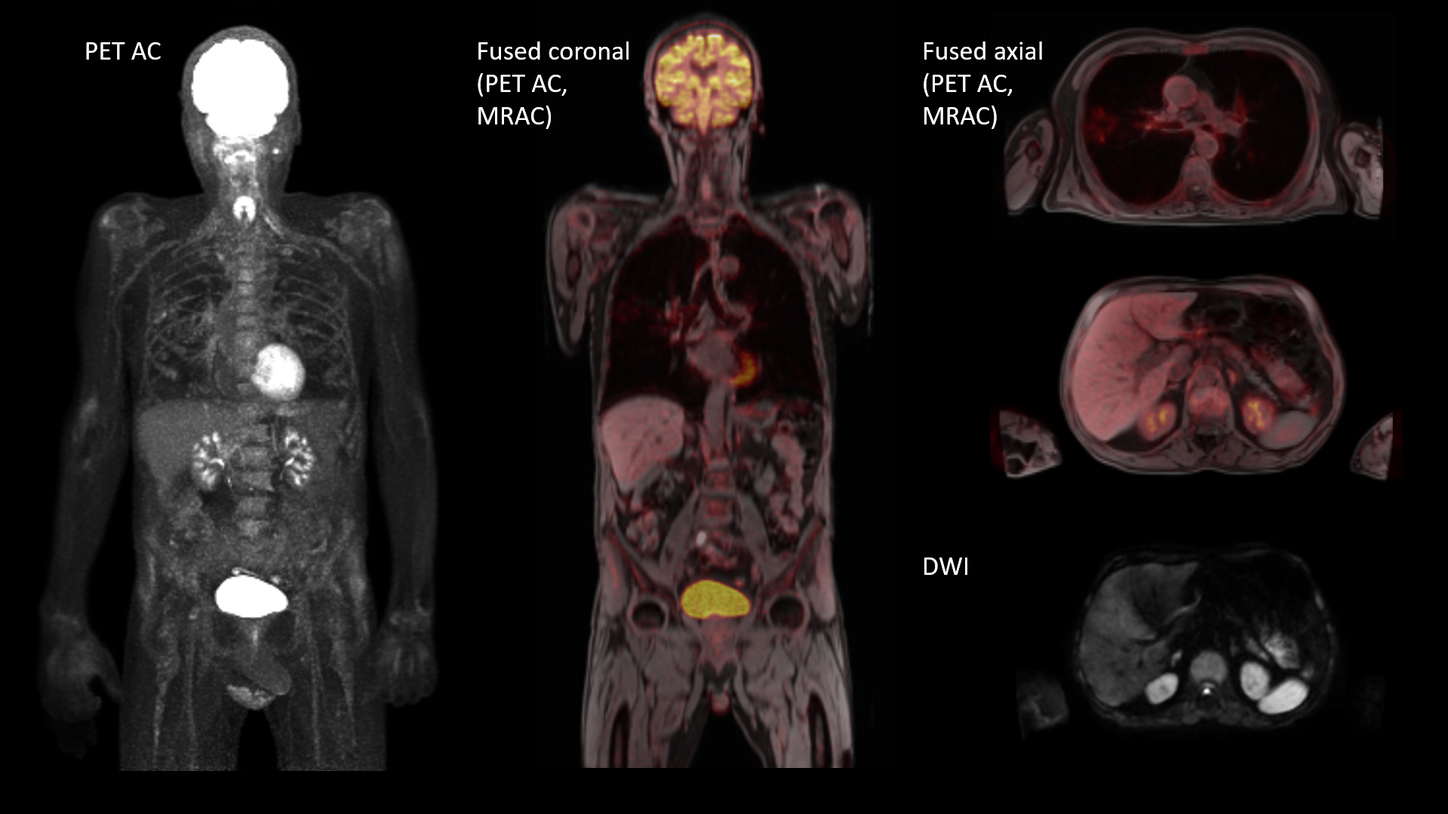

BIOGRAPH One is designed to support one patient-centric pathway to personalized care. By seamlessly integrating PET and MR into one comprehensive exam, it will support clinicians from diagnosis and staging, through a personalized therapy decision to regular therapy assessments to excel precision and support one streamlined approach.

BIOGRAPH One is designed to excel in PET/MR precision to support confident diagnostic decisions. Featuring the Optiso UDR Pro detector with the largest 35 cm axial FOV2 in PET/MR, it is designed to enable comprehensive capture with excellent sensitivity and ultra-fast TOF3 in real time – delivering clear, detailed images.

Planned with Deep Resolve for accelerated acquisition and improved resolution in 2D and 3D applications4, BIOGRAPH One has the potential to make PET/MR exams faster than ever before. Designed with a powerful 3T magnet at its heart, BIOGRAPH One will deliver unparalleled performance with outstanding homogeneity, a large 55 x 55 x 50 cm³ field of view and robust gradient power.